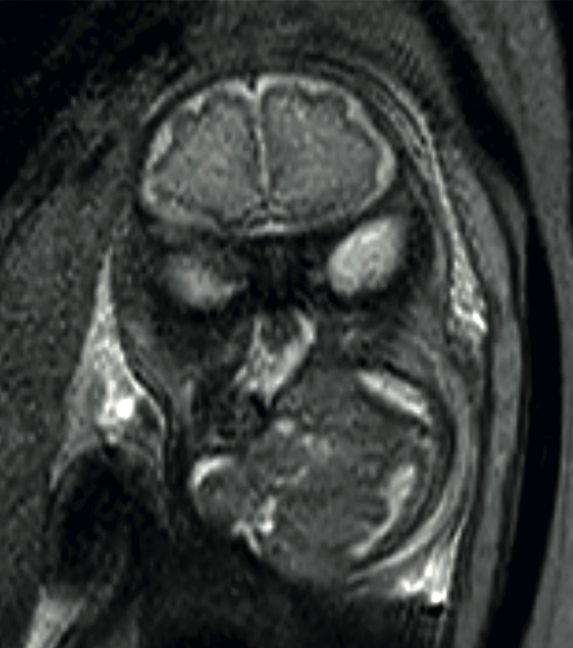

<strong>Figura 2</strong>

Figura 2. Resonancia a las 35 semanas, secuencia T2. Se observa una lesión heterogénea mixta, quística-sólida, en el hemicuello izquierdo, con extensión al piso de la boca y desplazamiento de la vía aérea.